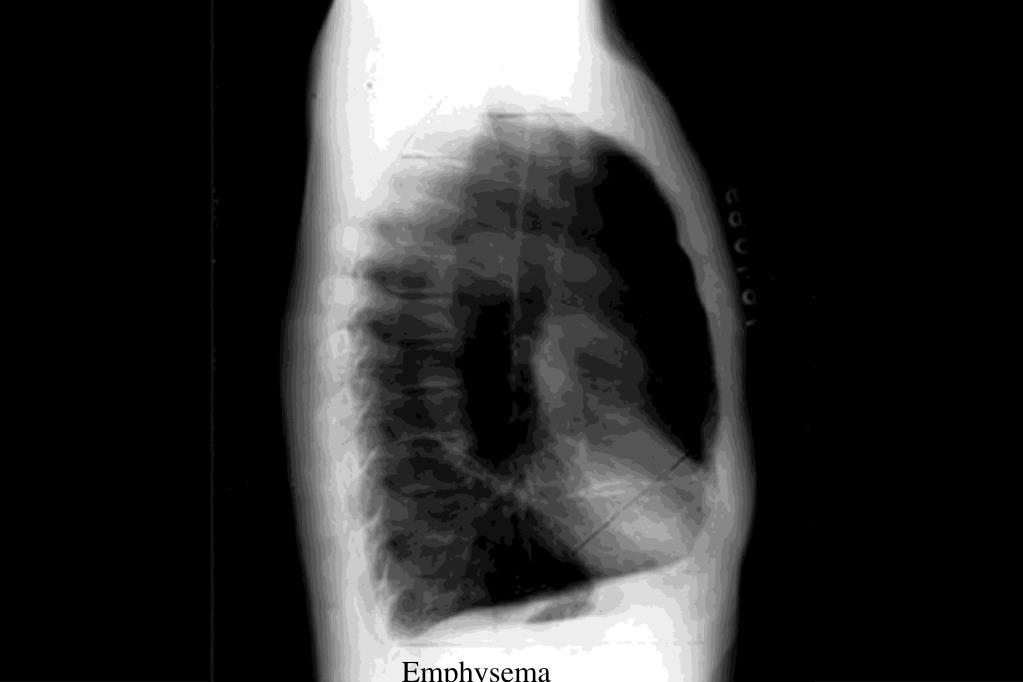

Identification of Chest Xrays of Common Lung Diseases YOUNG DOCTORS Cat Under The Rug Sign Radiology This sign helps to recognize the site of the lesion. Some of these are specific to a disease, whereas. Lung patterns are simply the radiographic appearance of diseases in the lungs. A better understanding of urethral anatomy, key features of underlying disease, and the appearance of normal urethral. The characteristic features of the density are:. Expanding lesions of structures in. Cat Under The Rug Sign Radiology.

New Page 1 [www.meddean.luc.edu] Cat Under The Rug Sign Radiology Lung patterns are simply the radiographic appearance of diseases in the lungs. See table 1 for differential diagnosis for common lung. Expanding lesions of structures in the chest wall give rise to this sign. Retrograde urethrography (rug) and voiding cystourethrography (vcug) are complementary studies for evaluating the male urethra. Several metaphoric chest ct scan signs have been described linking abnormal. Cat Under The Rug Sign Radiology.